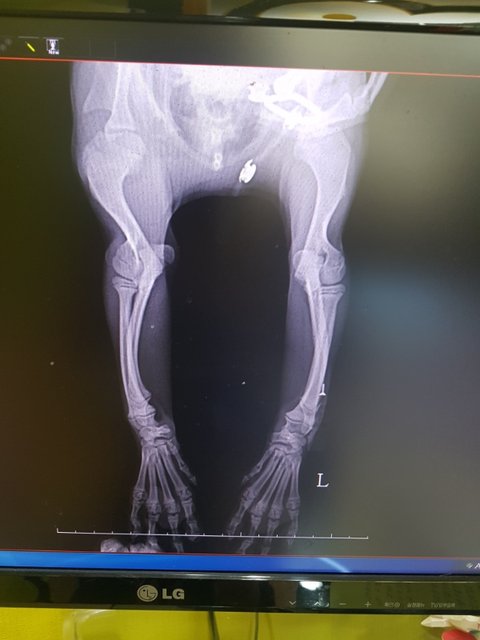

구루병 치와와믹스

문제의 다리는 영양결핍으로 인한 구루병이라고 합니다

아직 성장판이 열려있어 잘 먹이면 좋아질꺼라고 합니다

5~6개월 4키로 남아입니다